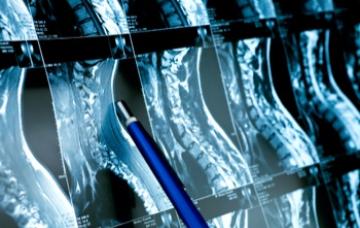

Diagnóstico del cáncer óseo

El diagnóstico del cáncer óseo se realiza mediante las siguientes técnicas: radiología simple, TAC, resonancia, y a veces biopsia o estudios de extensión.